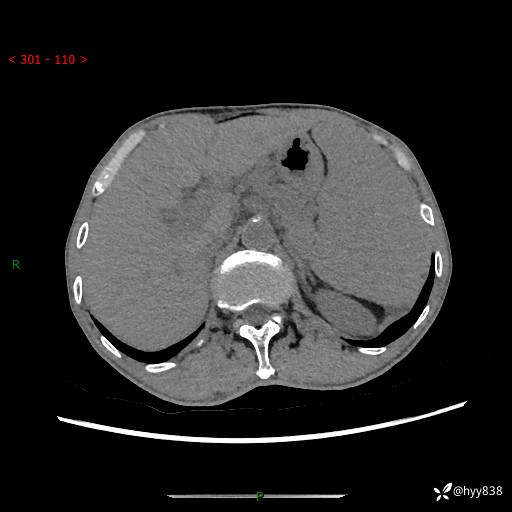

老年男性,脾大并脾脏弥漫粟粒状低密度,淋巴瘤 VS 肉芽肿 VS 血管瘤---结果公布

简要病史: 患者于3月前无明显诱因出现脾大,伴腹部轻微不适,具体不详,无腹痛、腹泻、腹胀,无头晕、头痛、乏力,无恶心、呕吐、呕血,无胸闷、气短、胸痛不适

上腹部CT平扫+增强